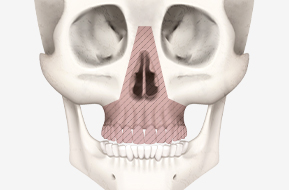

위턱이 과도하게 돌출되었거나

꺼져 있는 경우,

적절한 위치로 이동시켜

안모의 균형을 맞추는 수술입니다.

콧볼 정도의 위치에서

위턱 뼈를 절단하는 수술법으로

기본적인 상악 수술법

본원의 정필훈 이사장님

(서울대 치과대학 구강악안면외과 명예교수)이

직접 개발한, 코뼈를 포함하는 형태의

구강 내 상악 수술법